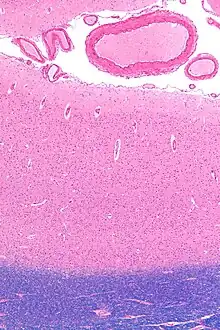

The primary visual cortex, which is defined by its function or stage in the visual system, is approximately equivalent to the striate cortex, also known as Brodmann area 17, which is defined by its anatomical location. The name "striate cortex" is derived from the line of Gennari, a distinctive stripe visible to the naked eye.

It's worth noting that Brodmann area 17 is just one subdivision of the broader Brodmann areas, which are regions of the cerebral cortex defined based on cytoarchitectural differences. In the case of the striate cortex, the line of Gennari corresponds to a band rich in myelinated nerve fibers, providing a clear marker for the primary visual processing region.

Additionally, the functional significance of the striate cortex extends beyond its role as the primary visual cortex. It serves as a crucial hub for the initial processing of visual information, such as the analysis of basic features like orientation, spatial frequency, and color. The integration of these features in the striate cortex forms the foundation for more complex visual processing carried out in higher-order visual areas. Recent neuroimaging studies have contributed to a deeper understanding of the dynamic interactions within the striate cortex and its connections with other visual and non-visual brain regions, shedding light on the intricate neural circuits that underlie visual perception.[13] that represents myelinated axons from the lateral geniculate body terminating in layer 4 of the gray matter.

The primary visual cortex is divided into six functionally distinct layers, labeled 1 to 6. Layer 4, which receives most visual input from the lateral geniculate nucleus (LGN), is further divided into 4 layers, labelled 4A, 4B, 4Cα, and 4Cβ. Sublamina 4Cα receives mostly magnocellular input from the LGN, while layer 4Cβ receives input from parvocellular pathways.[14]